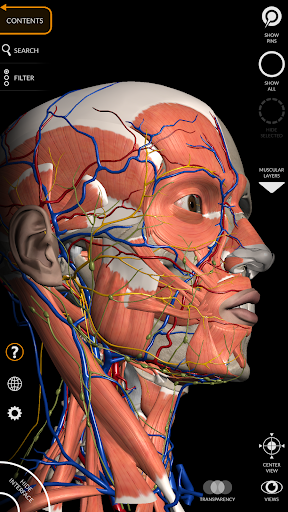

"Anatomía - Atlas 3D" permite estudiar la anatomía humana de forma fácil e interactiva.

A través de una interfaz sencilla e intuitiva es posible observar cada estructura anatómica desde cualquier ángulo.

Los modelos anatómicos 3D son especialmente detallados y con texturas de hasta una resolución de 4k.

La subdivisión por regiones y las vistas predefinidas facilitan la observación y el estudio de partes individuales o grupos de sistemas y las relaciones entre los diferentes órganos.

• Sistema musculoesquelético

nervioso • Sistema respiratorio • Sistema digestivo • Sistema urogenital (masculino y femenino) • Sistema endocrino • Sistema linfático • Sistema ocular y auditivo CARACTERÍSTICAS • Interfaz sencilla e intuitiva • Rotar y hacer zoom en cada modelo en el espacio 3D • Opción para ocultar o aislar uno o varios modelos seleccionados • Filtro para ocultar o mostrar cada sistema • Función de búsqueda para encontrar fácilmente cada parte anatómica • Función de marcador para guardar vistas personalizadas • Rotación inteligente que mueve el centro de rotación automáticamente • Función de transparencia • Visualización de músculos a través de niveles de capas desde las superficiales hasta las más profundas • Al seleccionar un modelo o un pin, aparece el término anatómico relacionado • Descripción de los músculos: origen, inserción, inervación y acción • Mostrar/ocultar interfaz de usuario (muy útil con pantallas pequeñas) MULTILINGÜE • Los términos anatómicos y la interfaz de usuario están disponibles en 11 idiomas: latín, inglés, francés, alemán, italiano, portugués, turco, ruso, español, Chino, japonés y coreano • Los términos anatómicos se pueden mostrar en dos idiomas simultáneamente REQUISITOS DEL SISTEMA • Android 8.0 o posterior, dispositivos con al menos 3 GB de RAM Reversi